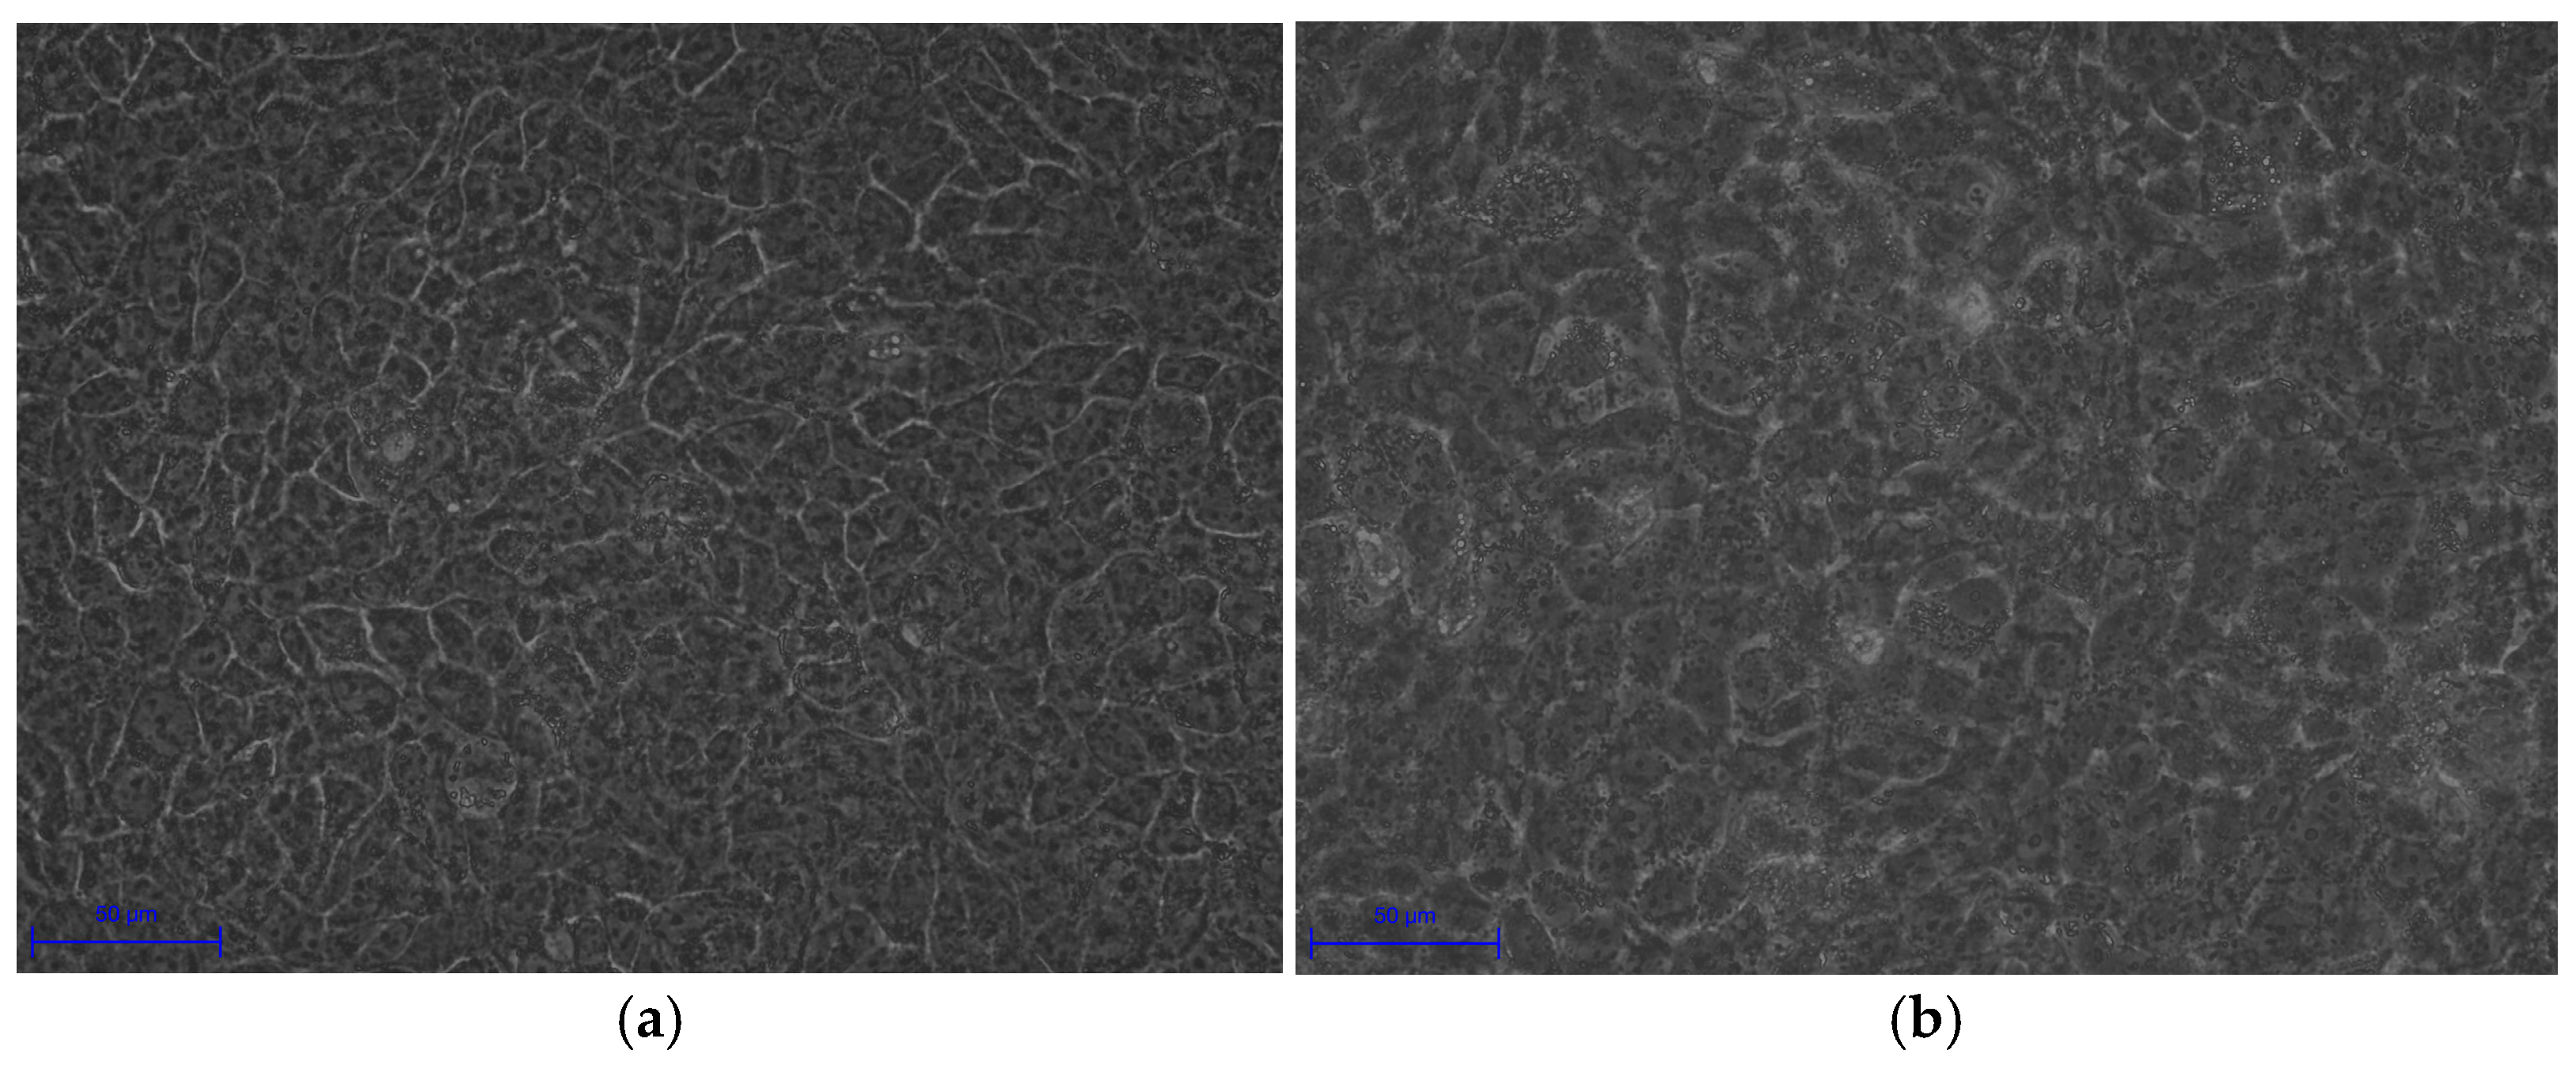

Experimental validation corroborated these transcriptomic insights. Morphological changes in infected HaCaT cells, including cell swelling (area: 250.08 ± 17.28 μm

2 vs. 135.78 ± 20.42 μm

2,

p < 0.0001) and irregular boundaries, indicate cytoskeletal disruption and potential apoptosis, consistent with

C. acnes IA

1–induced stress (

Table 5). Fluorescence microscopy revealed biofilm formation by